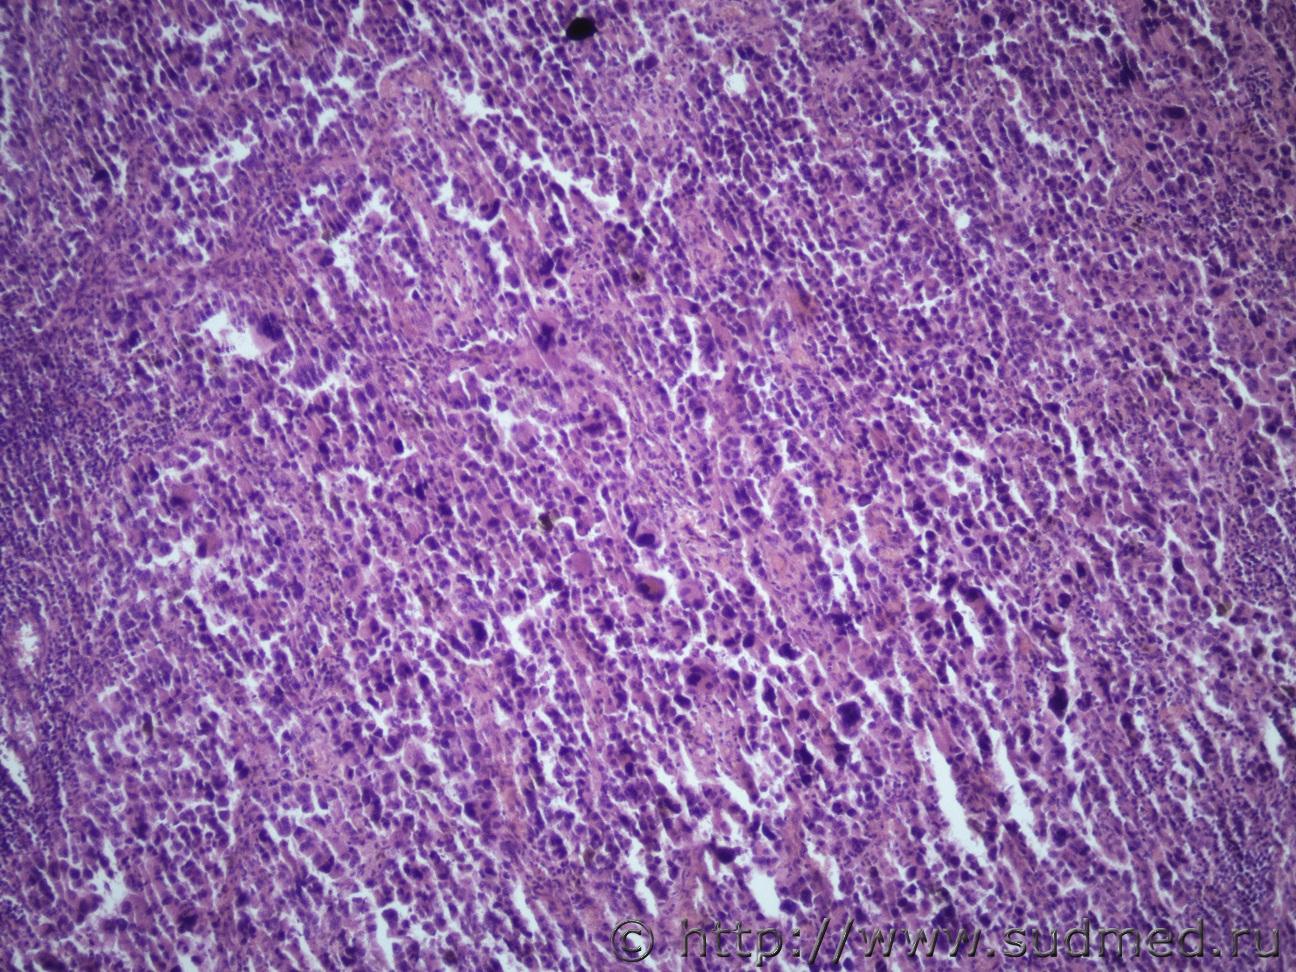

Ув. коллеги доброго дня. Представляю опухоль мочки пр. ушной раковины (9х5х4 см).Судебная медицина - Прикрепленное изображение Судебная медицина - Прикрепленное изображениеСудебная медицина - Прикрепленное изображениеСудебная медицина - Прикрепленное изображениеСудебная медицина - Прикрепленное изображение

Первое,что приходит на ум - это меланома,но надо ещё deal1.gif .

Соглашусь с ув. Медиком. Тоже подумал в первую очередь о меланоме.

Похоже на гигантскую ювенильную ксантогранулему.

Чем ?

Не вижу ксантомных клеток и эозинофилов.

Ювенильная ксантогранулёма встречается главным образом у детей,а в консультируемом случае,скорее всего, умерший недетского возраста.

Да, возраст 65 лет

Тогда соответствует картине Атипической фиброксантоме(AFX)